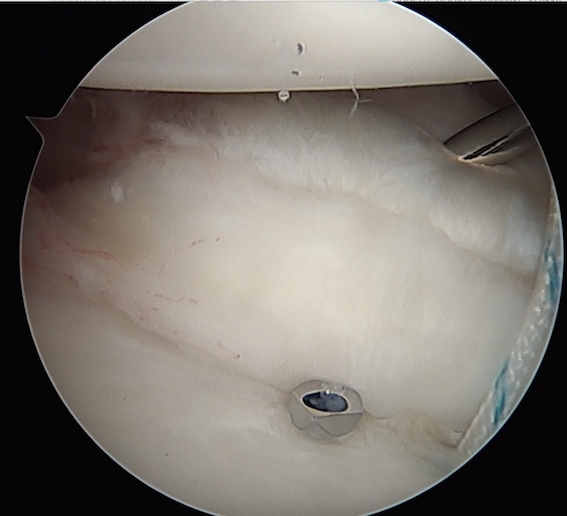

Anterior capsular plication with sutures

Anterior capsular plication with suture anchors